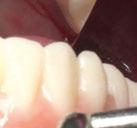

Exploración Intraoral

Presenta un estado oral deficitario. Parcialmente edéntula, con colapso de mordida, migración dental patológica, restauraciones de resina antiguas fisuradas y filtradas, transparencia y exposición de cámara pulpar secundaria a desgastes con pérdida de estructura e integridad de tejido dental importante (Figuras 1 a 4). Portadora a tiempo parcial de prótesis removibles desadaptadas de más de 10 años de antigüedad, refiriendo incapacidad de adaptación a este tipo de prótesis.

Figura 3. Visión intraoral oclusal mandibular. Figura 4. Visión intraoral frontal. Figura 1. Visión intraoral oclusal maxilar. Figura 2. Visión lateral izquierda intraoral. Figura 7. Escaneado intraoral maxilar con Dexis IS3700. Figura 8. Escaneado intraoral mandibular con Dexis IS3700. Figura 5. Visión extraoral lateral sonrisa.